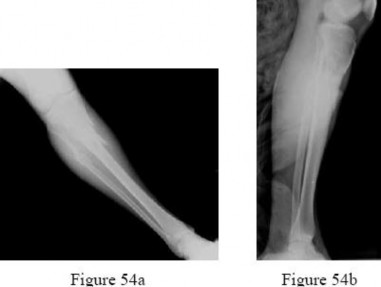

are the radiographs of a 23-year-old man who fell from a height and sustained an isolated injury to his right leg. Which of the following is a useful surgical technique to optimize alignment during intramedullary nailing?